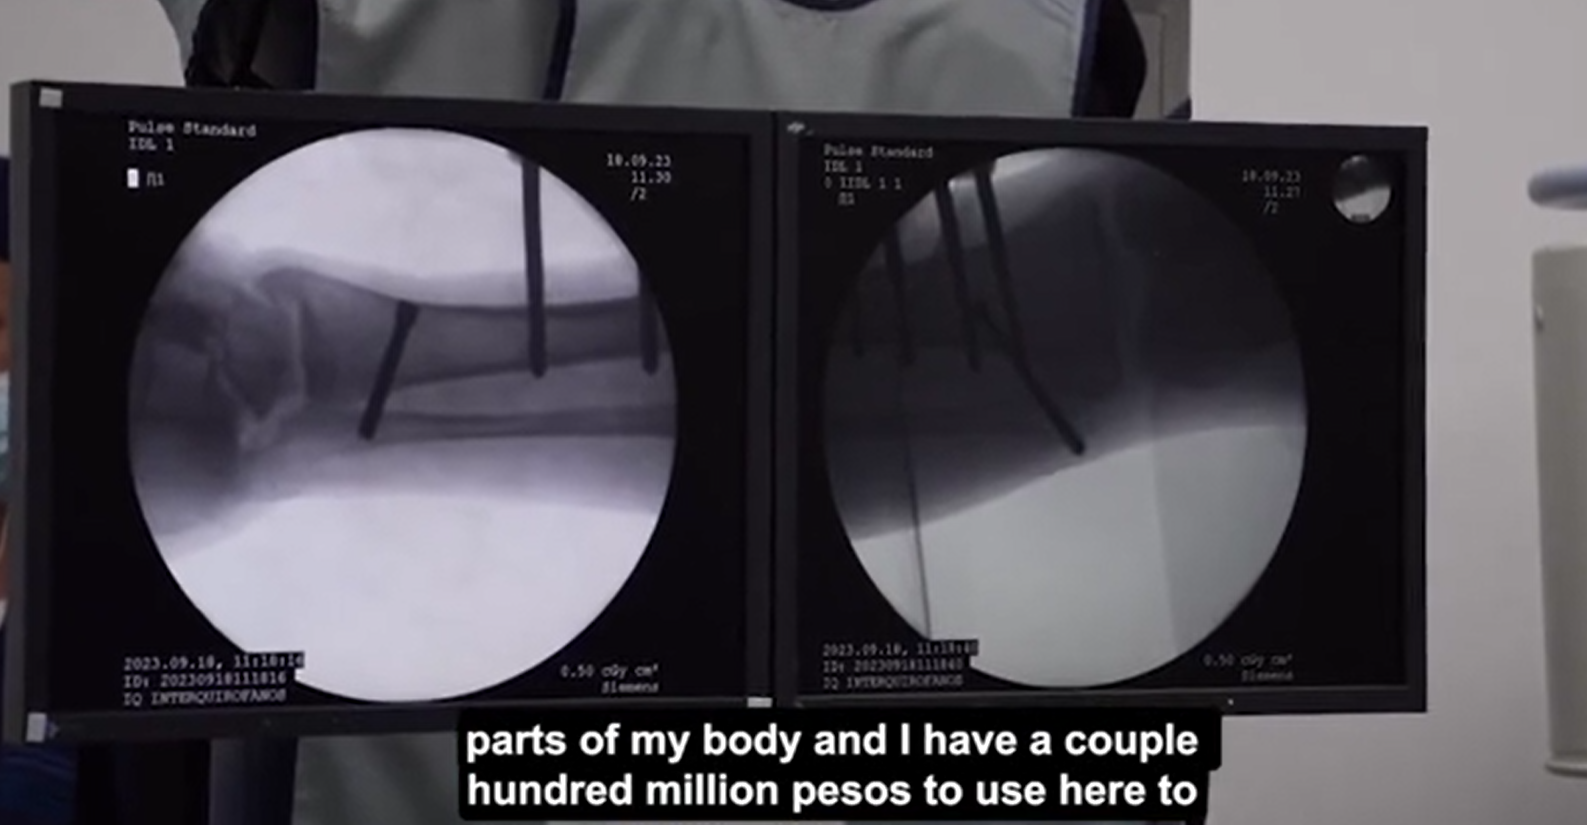

29歲男網紅科西奧(Yeferson Cossio)本身已有5呎8吋高,他說因有不方便說明的腳患問題,而決定在首都波哥大(Bogota)一診所做斷骨增高手術。手術涉及把其腿骨斷開,再加上金屬磁力支架,之後再用遙控方式將支架逐少伸長,拉長腿骨及肌肉組織。目前Cossio已接受手術4個月,據報每天可以增高約1毫米,若一切順利,他最終可以增高4吋。